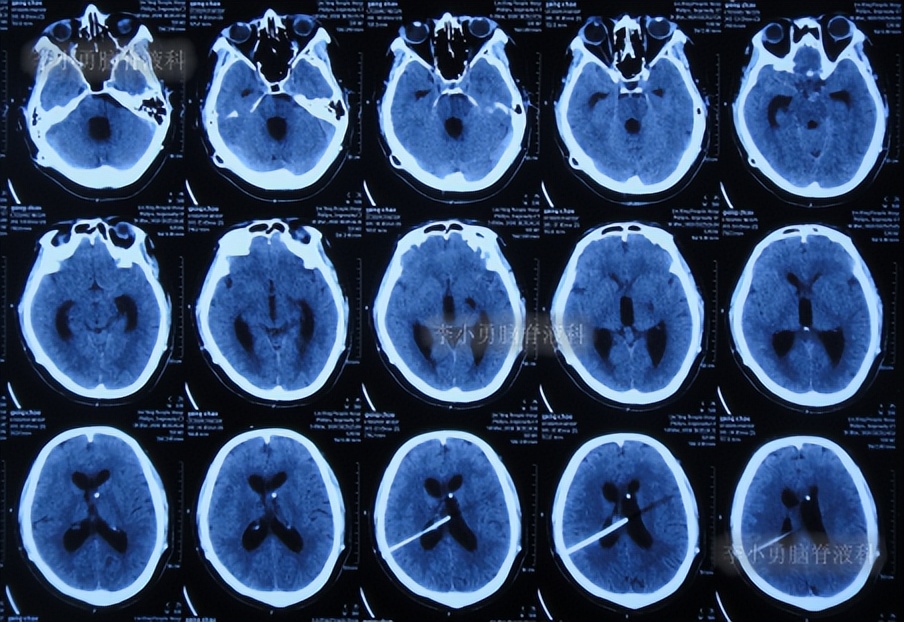

二、第1次在李小勇脑脊液科治疗过程和结果

2020年6月4日(脑囊虫切除术+第三脑室造瘘术后2年5个月,2次脑室腹腔分流术均堵管,期间历经5次住院但脑积水仍反复复发)住入李小勇脑脊液科,入院时:神志朦胧,饮食差,问答有误,自己站立不稳,双眼对视(图-19);既往史:口服抗癫痫药物,青霉素过敏。头颅CT示鞍上占位术后,脑室内可见引流管,脑室系统扩张(图-20)。

图-20:2020年6月4日头颅CT